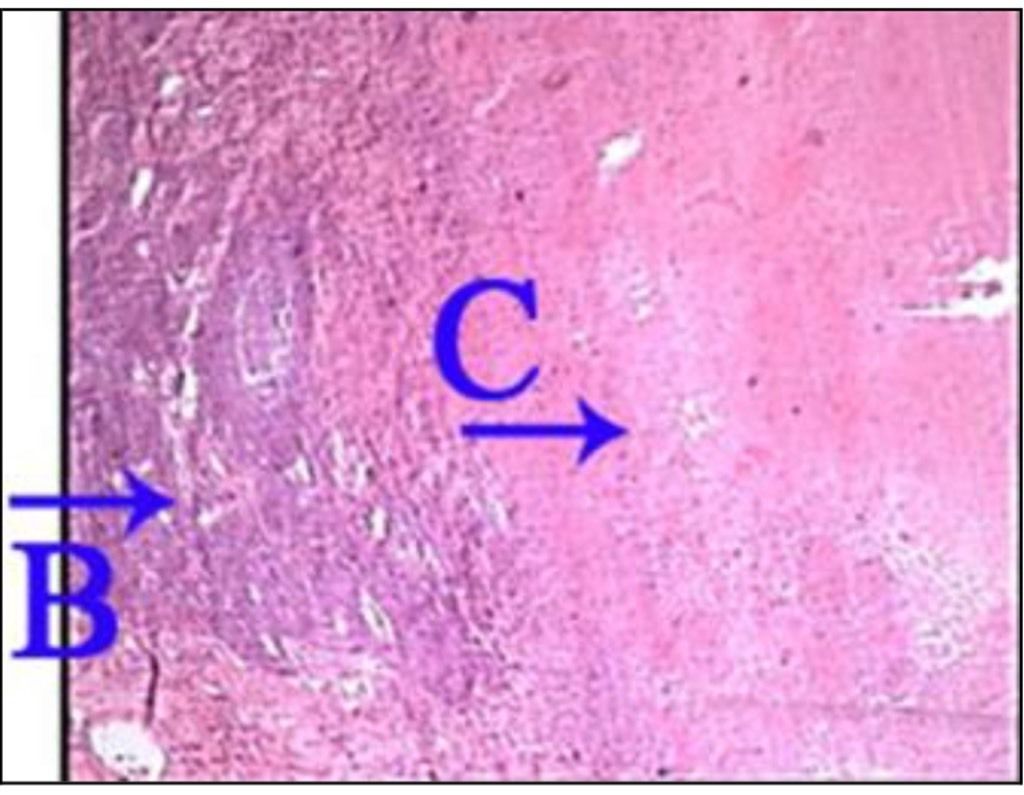

Question 102

Question

What is the correct answer at point A?

Answer

• - granulome tuberculoïde

• - tissu lymphoïde

• - plage de nécrose caséeuse

• - cellule géante de Langhans

• - cellule épithélioïde

Question 103

What is the correct answer at point B?

Question 104

What is the correct answer at point C?

Question 105

What is the correct answer at point D?

Question 106

What is the correct answer at point E?